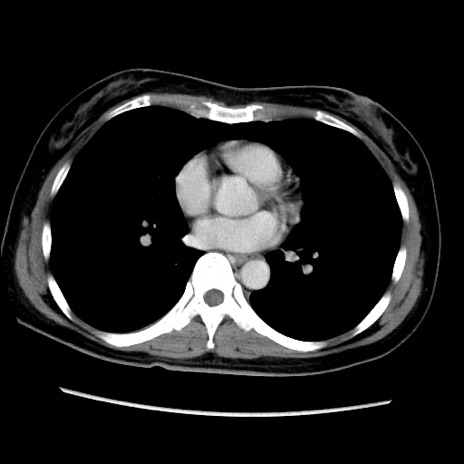

症例39(横断像)

【症例】40歳代女性

【主訴】上下腹部痛

【現病歴】2日目から下腹部痛あり。夜間は痛みで眠れなかった。昨日より上腹部痛と下痢が出現。臥位で痛みは軽快したため、休んでいた。本日になって臥位でも立位でも痛みが強くなってきたため救急要請。

【既往歴】子宮内膜症

【身体所見】部:平坦・軟、左上下腹部に圧痛あり、反跳痛あり。

【データ】WBC 21800、CRP 26.78